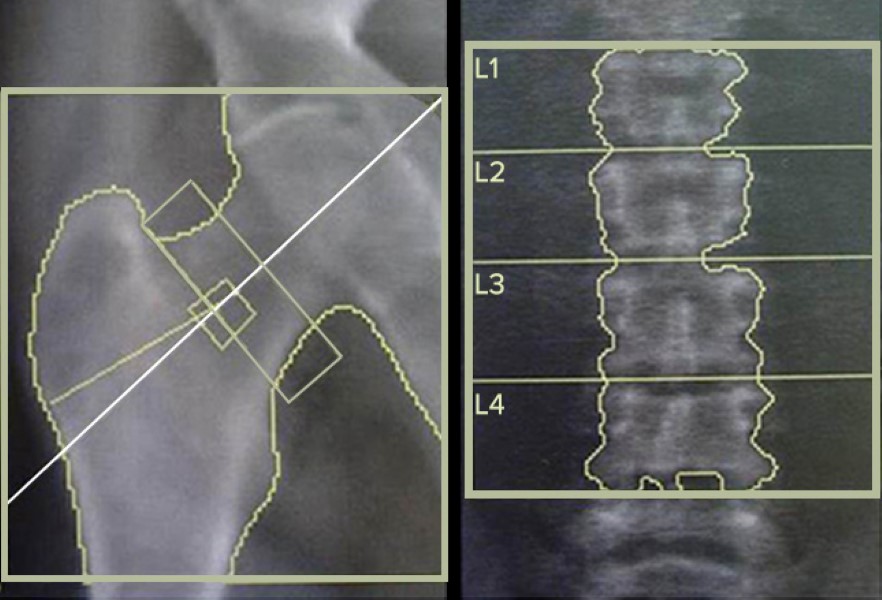

To study these differences, the researchers enrolled 532 male patients in their study who were already receiving care at the VA North Texas Health Care System. These patients were placed into four different groups that included those infected with both HIV and HCV, those only infected with HIV, those only infected with HCV, and uninfected veterans (used as controls for the study). These patients all underwent both bone mineral density testing (the old method for testing bone health) as well as trabecular bone score testing (the new method of testing bone health) on the lumbar portion of their spine, the head of their femur, and their hips.

After taking into account each patient’s age, race, body mass index, and smoking status (traditional risk factors for poor bone health), the researchers confirmed previous studies that people infected with both viruses tend to have lower bone density than healthy people. However, the trabecular bone scores were able to show more detail. The researchers found that while there was no difference in trabecular bone scores between HIV positive patients and healthy patients, HCV-infected patients did show poorer scores. Furthermore, patients with both HIV and HCV infection had lower trabecular bone scores than all other patient groups.